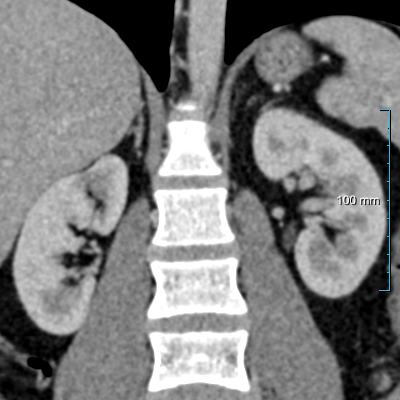

Refer to caption

(a) Input CT scan

(b) Annotations format 1

(c) Annotations format 2

Figure 2: Example illustrating the different annotation formats. Each subfigure shows the same axial section, with overlays depicting the annotations: (a) shows the axial CT section. (b) shows the annotations in format 1: parenchyma and kidney abnormalities as a single structure (yellow overlay). (c) shows the annotations in format 2: parenchyma (yellow overlay) and kidney abnormalities (red overlay) as different structures. All images have a window center of 60 HU and a window width of 360 HU.

This study utilized two annotation formats, format 1 and format 2, to store the annotations. Format 1 considers the kidney parenchyma and kidney abnormalities as a single class (see Figure 2(b)) while format 2 separates them into two classes (see Figure 2(c)).